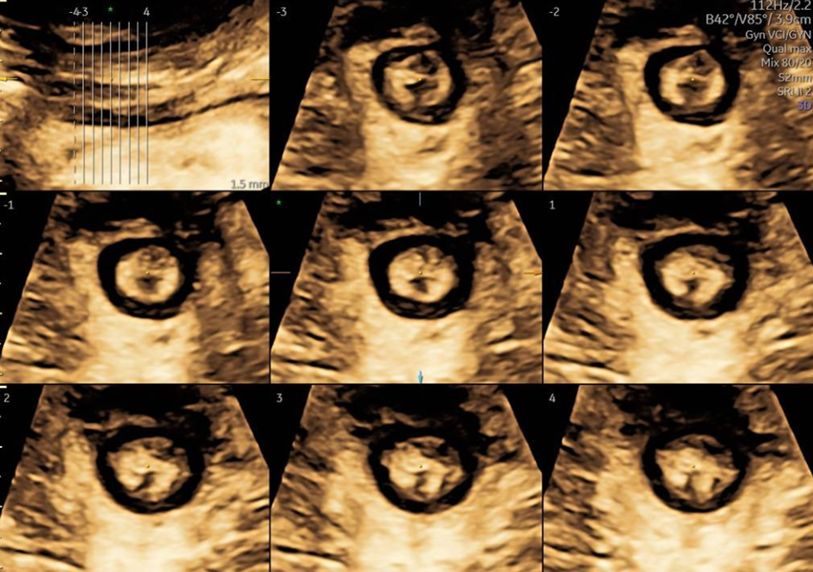

Eseguo in particolare ecografie ostetriche e ginecologiche anche in 3D e 4D per meglio identificare la problematica, offrire diagnosi precise ed un trattamento mirato e personalizzato.

• Arcispedale Santa Maria Nuova - IRCSS Reggio Emilia ecografia ostetrica 3D/4D  •